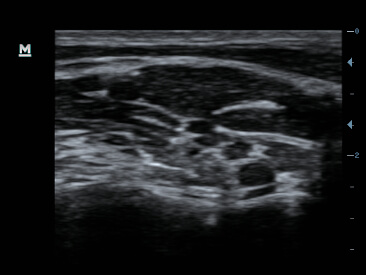

Gambar Klinis